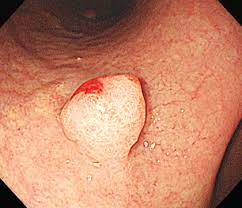

위용종은 위점막에 있는 상피세포가 자라서 솟아올라온 버섯 같은 모양을 가진 혹을 말합니다. 조직학적 특성에 따라서 분류하기도 하는데, 염증성 용종, 과증식성 용종 그리고 선종성 용종으로 분류할 수 있습니다.

보통 전체 위용종의 90%이상 정도는 과증식성 용종에 해당되어 대부분 2cm 이하로 자라며, 암으로 까지 진행되는 경우는 아주 드물기 때문에 보통 6개월에서 1년마다 위내시경으로 경과를 관찰합니다. 보통 2cm 이상으로 크기가 큰 경우에는 빈혈이나 소화불량 등의 증상이 나타나므로 제거하는 것을 추천합니다.

위 용종은 보통 위조영 X-ray나 상부 위장관 내시경 검사로 진단합니다. 위 내시경은 입을 통과하여 식도 아래를 거쳐 위, 십이지장을 내시경 끝에 달린 카메라를 통해 연결된 화면으로 관찰하는 방법입니다. 위 내시경은 용종의 모양 및 크기를 직접 볼 수 있어 진단에 유리하고, 이상 시 조직 생검(biopsy)을 통해 조직학적(병리학적) 진단을 내릴 수 있습니다.

위용종은 대부분 양성 이지만, 크기나 형태에 따라서 암으로 발전할 가능성이 있기 때문에, 적절한 치료가 필요합니다. 보통 용종의 크기가 2cm 이상인 경우나, 염증성 용종, 과증식성 용종은 내시경을 이용하여 제거하는 것이 적절합니다. 암으로 진행이 될 가능성이 높은 선종성 용종일 경우에는 반드시 제거를 해야 합니다.